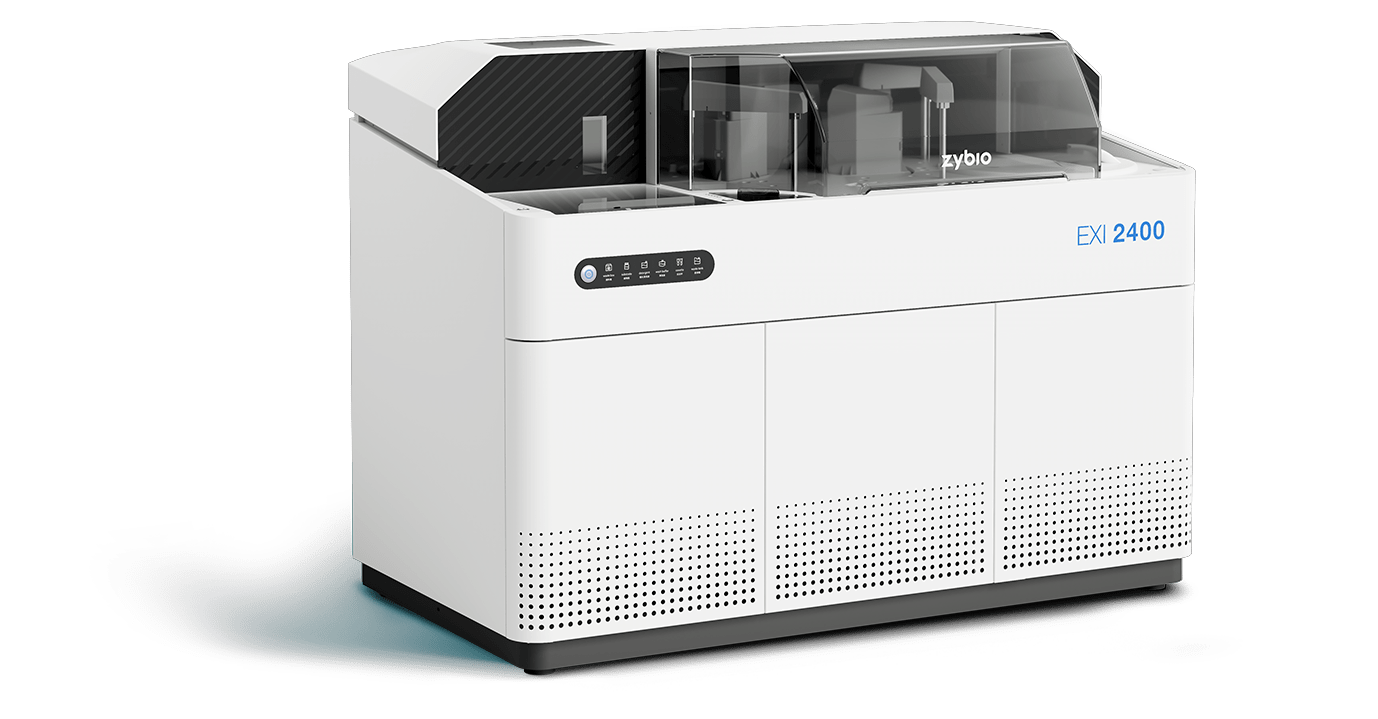

EXI 2400

全自动化学发光免疫分析仪

400 T/H

单机检测速度

13 min

首结果时间

28 个

试剂位

100 个

样本位

1200 个

反应杯一次存储量